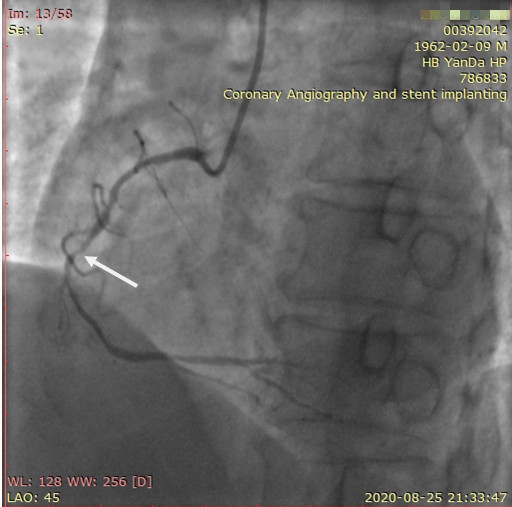

李先生右冠术前影像

李先生右冠术后影像